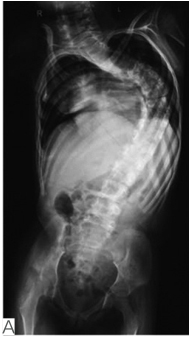

图5远端关节挛缩合并脊柱侧凸患者,6岁,女孩

A.术前全脊柱正位片提示大C型胸弯;B.行单侧可撑开型脊柱内固定手术,术后全脊柱正侧位片提示侧凸部分矫正,躯干平衡尚可;C.术后外观照(引自Komolkin I, et al. Treatment of Scoliosis Associated With Arthrogryposis Multiplex Congenita. J Pediatr Orthop, 2017,37 Suppl 1:S24-S26.)